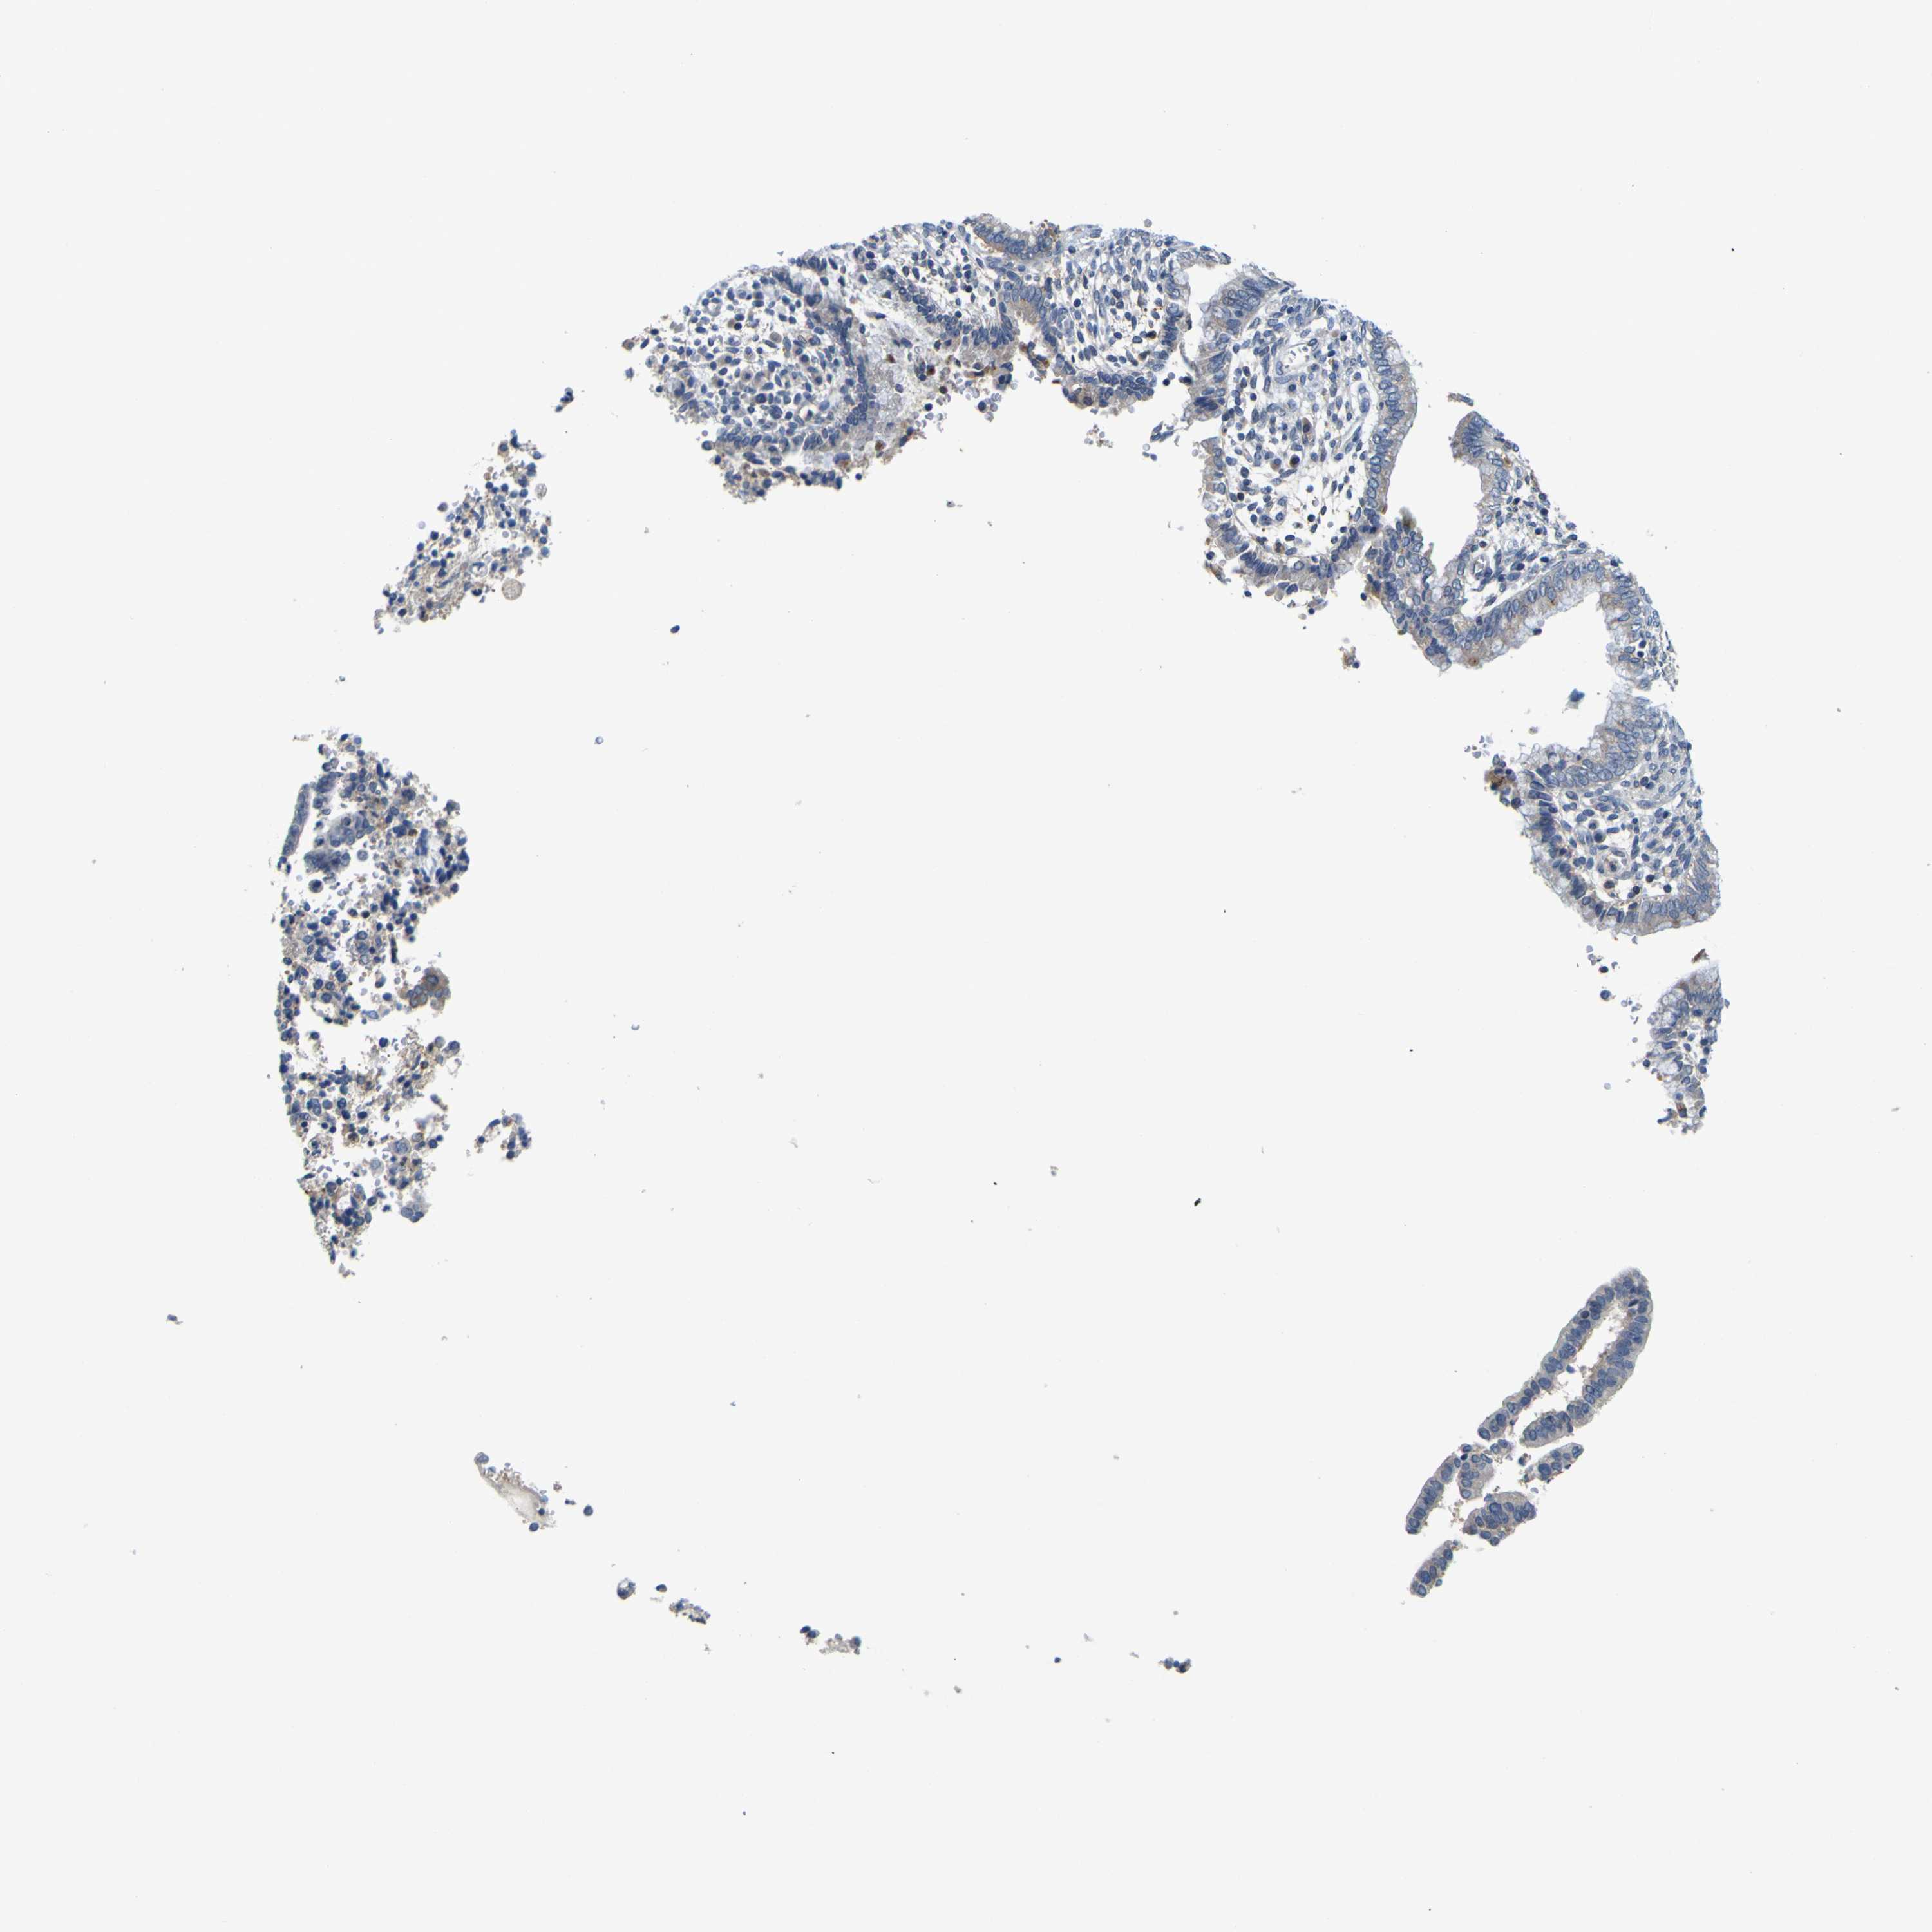

CERVICAL CANCER - Protein expressioni

A mouse-over function shows sample information and annotation data. Click on an image to view it in a full screen mode. Samples can be filtered based on level of antibody staining by selecting one or several of the following categories: high, medium, low and not detected. The assay and annotation is described here.

Note that samples used for immunohistochemistry by the Human Protein Atlas do not correspond to samples in the TCGA dataset.

Antibody stainingi

Antibody staining in the annotated cell types in the current human tissue is reported as not detected, low, medium, or high, based on conventional immunohistochemistry profiling in selected tissues. This score is based on the combination of the staining intensity and fraction of stained cells.

Each image is clickable and will lead to virtual microscopy that enables deeper exploration of all samples and also displays staining intensity scores, fraction scores and subcellular localization as well as patient and tissue information for each sample.

Antibody HPA012128

Antibody HPA012297

Staining

High

Medium

Low

Not detected

Intensity

Strong

Moderate

Weak

Negative

Quantity

>75%

75%-25%

<25%

None

Location

Nuclear

Cytoplasmic/membranous

Cytoplasmic/membranous,nuclear

Squamous cell carcinoma, NOS

Adenocarcinoma, NOS